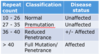

huntintons

CAG tri-nt repeat in HTT gene in chr 4

age of onset of huntington’s relationship

largers # repeats = earlier age of onset